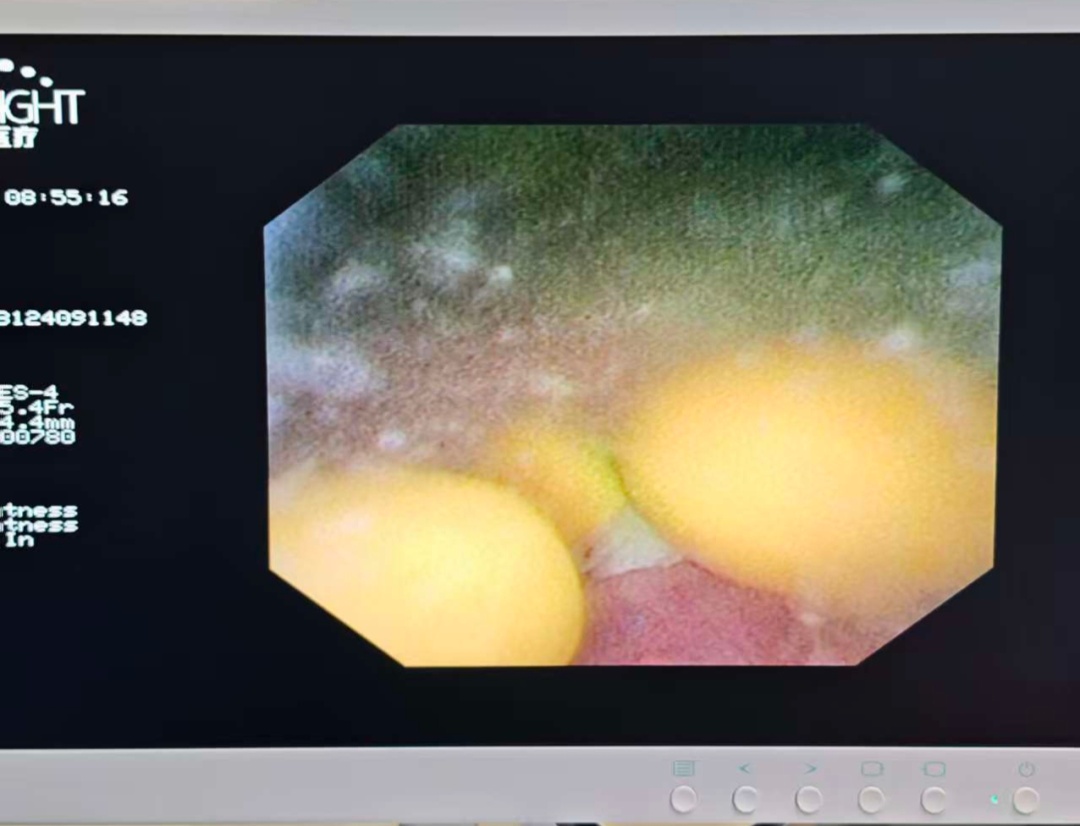

病情介绍 患者张先生(化名),77岁,因“尿频、尿急、尿痛伴血尿1天”来我院急诊。患者痛苦面容,自觉排尿困难且伴有肉眼可见的红色尿液,严重影响生活质量。 经检查发现,患者存在以下泌尿系统问题: 1.右侧输尿管结石伴有肾积水和感染 2.膀胱多发结石 3.前列腺增生 这些疾病相互影响,形成恶性循环:前列腺增生导致排尿不畅,尿液滞留形成膀胱结石;膀胱结石又可能堵塞尿道出口,加重排尿困难;而输尿管结石则阻碍尿液从肾脏排出,引起肾积水和感染,严重时可能影响肾功能甚至导致败血症。 治疗过程 面对这一复杂情况,区中医医院泌尿外科团队制定分期手术方案,确保治疗安全有效: 第一期手术:急诊处理,解除危机 手术名称:经尿道输尿管镜下膀胱结石钬激光碎石取石术+右侧输尿管支架置入术(双J管置入) 手术目的: 1.解除感染隐患:置入输尿管支架管,能立即疏通梗阻的右侧输尿管,引流出淤积的感染尿液,迅速控制感染,保护肾功能。 2.清除膀胱结石:同时处理已存在的膀胱结石,缓解部分下尿路症状。 此次手术快速、微创,核心目标是“控制感染、引流减压”,为后续根治性手术创造安全的身体条件和手术窗口期。 第二期手术:根治性处理,经过近两周的抗感染治疗和身体恢复,患者一般情况显著改善。 手术名称:经尿道右侧输尿管镜钬激光碎石取石术+前列腺电切术(TURP)+经尿道右侧输尿管支架置换术 手术目的: 1.粉碎输尿管结石:在支架管引导下,精准粉碎并取出造成梗阻的“元凶”——右侧输尿管结石。 2.切除前列腺:彻底切除增生的前列腺组织,从根源上解除下尿路梗阻,预防结石复发。 3.更换支架:确保输尿管通畅愈合。此次手术一举解决了所有根本性问题。 术后恢复 术后患者恢复顺利: 1.血尿、尿痛等症状消失。 2.困扰已久的尿频、尿急、夜尿增多等症状得到极大改善。 3.复查尿流率检查,结果完全恢复正常。 4.患者对治疗效果非常满意,由衷感谢我科团队精湛的技术和负责任的决策。 此次手术的成功,体现区中医医院处理复杂高危病例的丰富经验和先进理念: 1.精准决策:不盲目追求“一刀切”,而是根据“轻重缓急”原则,制定个体化的分期治疗方案。先解决急性、危及生命的问题(感染梗阻),再处理慢性、根源性问题(结石、前列腺增生),最大程度保障了患者安全。 2.技术的保障:两次手术均采用经尿道的微创方式,利用输尿管镜、电切镜等先进设备,体表无切口,创伤小,恢复快,非常适合高龄患者。 3.围术期管理:完善的术前准备、术中的麻醉配合、细致的术后护理,是患者能够平稳度过两次手术、顺利康复的坚实基础。 奉贤区中医医院 泌尿外科团队 专家提醒,老年男性出现以下症状时应及时就医: ·尿频、尿急、夜尿增多 ·排尿困难、尿流变细 ·血尿 ·腰背部疼痛 早期诊断和合理治疗能够有效保护肾功能,提高生活质量。我院泌尿外科在此类复杂泌尿系统疾病的微创治疗方面积累了丰富经验,为众多患者解除病痛。 王志伟 副主任医师 泌尿外科王志伟副主任医师,毕业于南昌大学医学院,医学硕士。2017年至上海长海医院泌尿外科进修学习、2022年至南昌大学第二附属医院泌尿外科进修学习。获2020年度医院十大好医生、医院优秀员工。主持完成市级科研课题2项,参与完成省级科研课题1项,两篇论文获得市级科协优秀学术论文二等奖。 擅长泌尿系统结石微创治疗,输尿管镜碎石取石术,电子输尿管软镜钬激光碎石负压取石术,彩超引导下经皮肾镜碎石取石术,泌尿系统感染的综合治疗,彩超引导下经会阴前列腺穿刺活检,前列腺增生微创手术,肾囊肿、肾肿瘤及前列腺肿瘤、膀胱肿瘤等泌尿系统肿瘤的诊治及微创手术治疗,及男性生殖相关疾病的诊治。 门诊时间 泌尿专科门诊: 周一全天,周二、周四、周五上午 王志伟副主任医师专家门诊: 周一上午、周三全天 便民咨询电话:57420861-8074